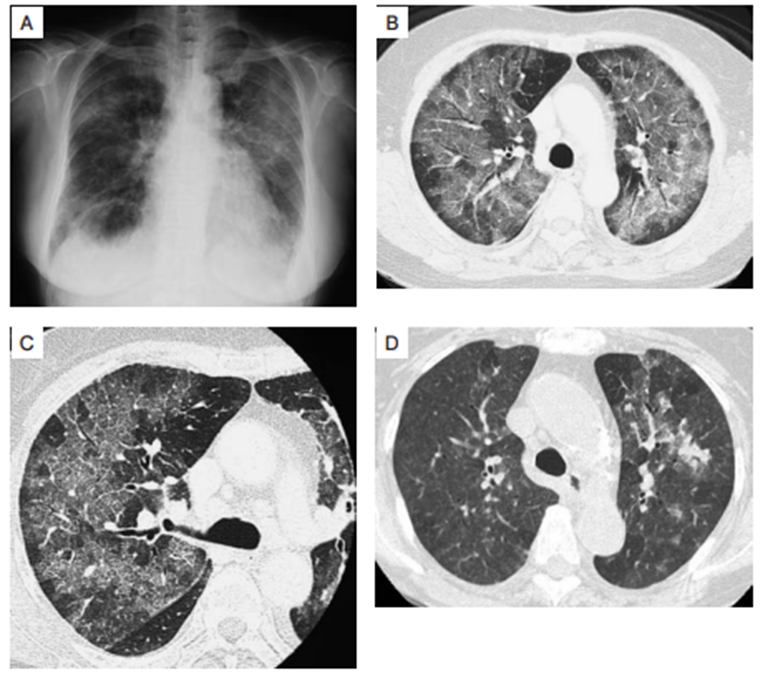

肺に炎症が起こることがあり、咳や息切れ、呼吸が苦しいなどの症状が現れる場合があります。風邪とは違って、息がきれる、空咳がでる、熱や倦怠感が続く、といった時は注意が必要です。早めに受診して検査を受けましょう。メトトレキサート肺炎 (図6) ということもあります。 - リンパ節腫脹(リンパ増殖性疾患)

原因によって治療方針が異なるため、早期の原因特定と初期対応が非常に重要です。図7に、評価方法と原因毎の治療をまとめます。ここでは、胸部X線や胸部CTといった画像評価が初期評価として重要であることが分かります。